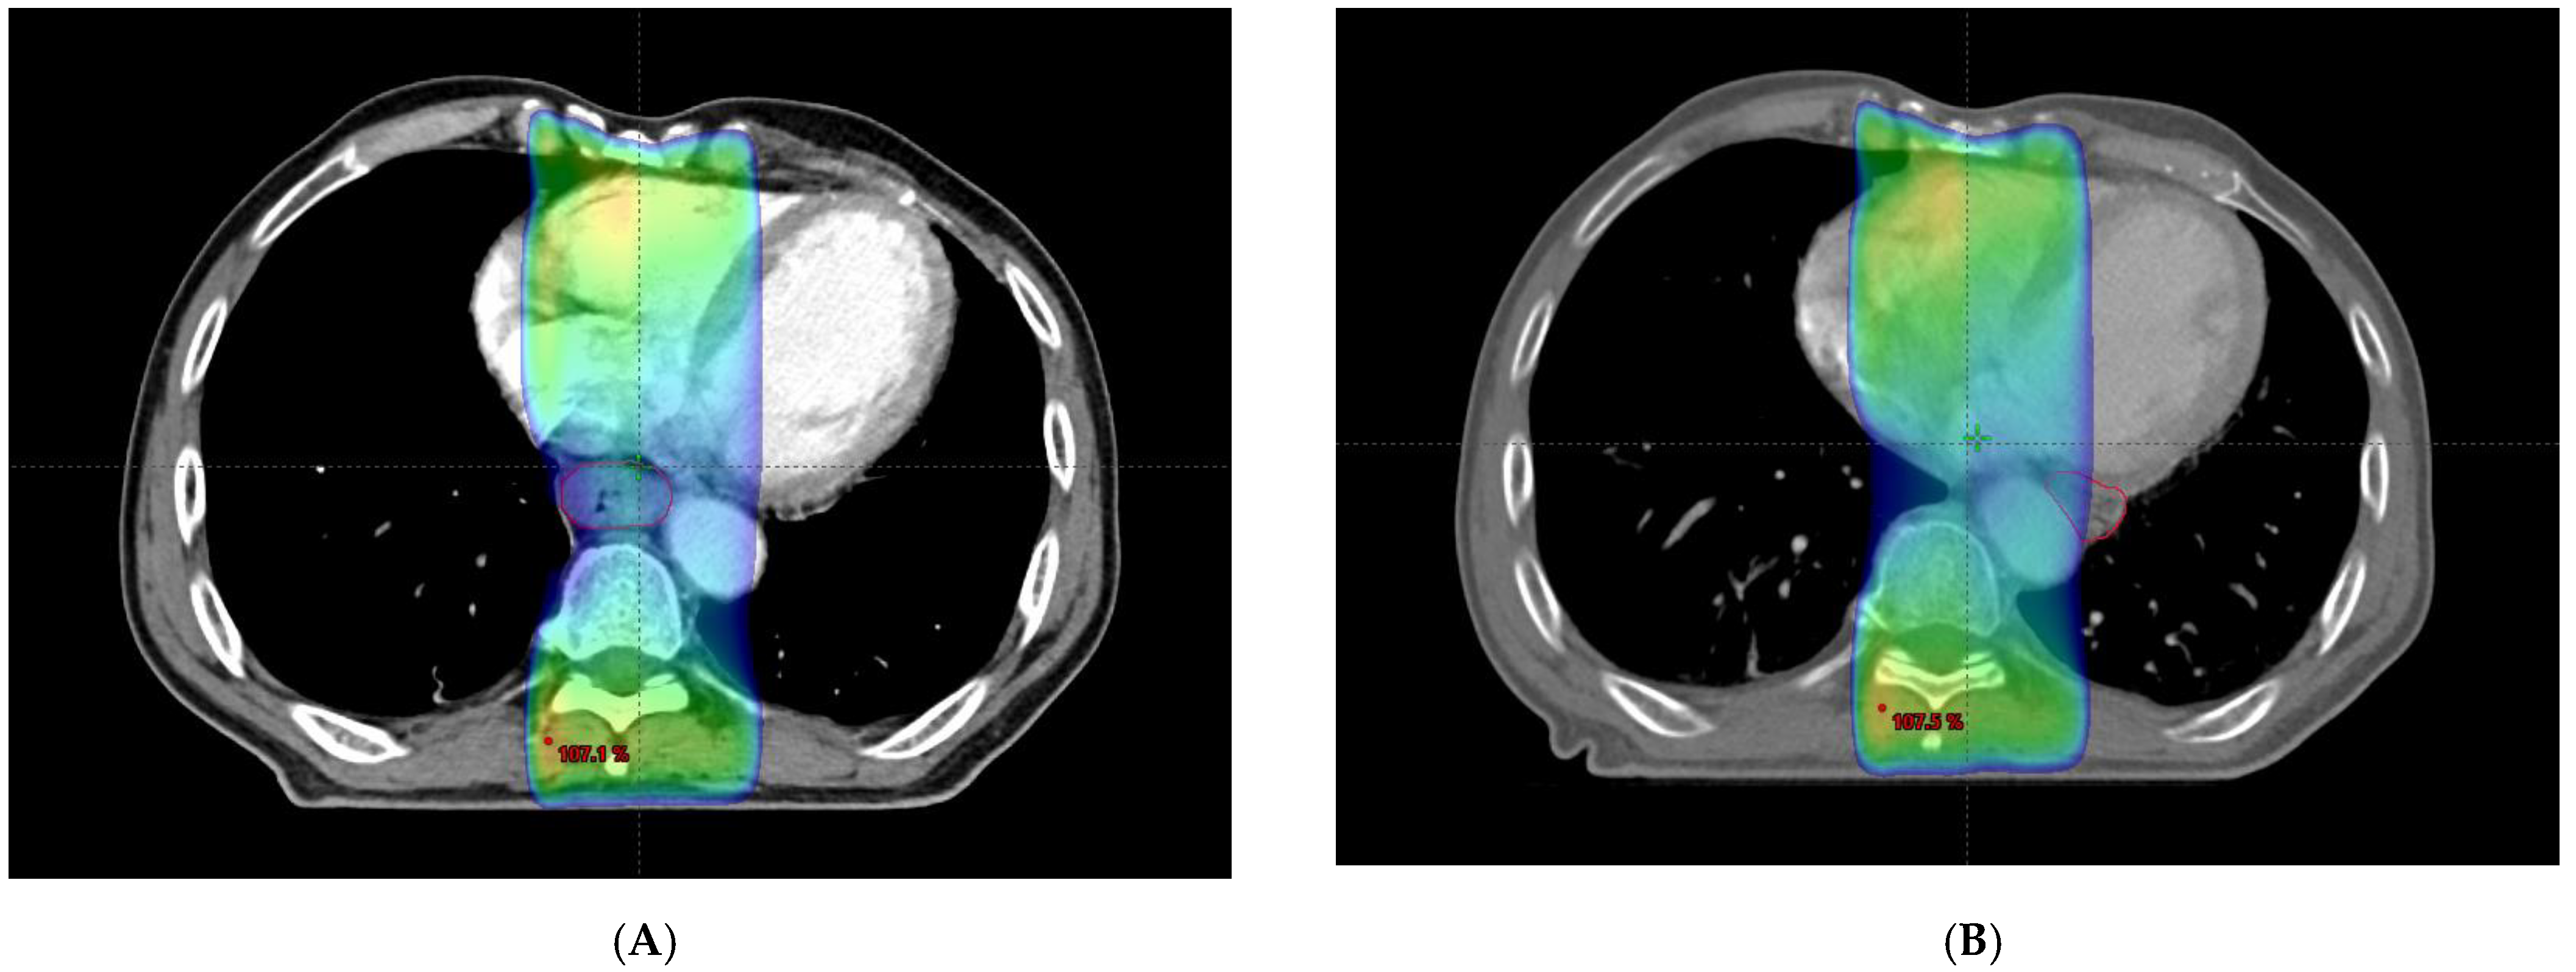

Unexpected Movement of the Esophagus across the Aorta

Choi, H.H.; Sung, S.-Y.; Ko, Y.H. Unexpected Movement of the Esophagus across the Aorta. Diagnostics 2022, 12, 1758. https://doi.org/10.3390/diagnostics12071758